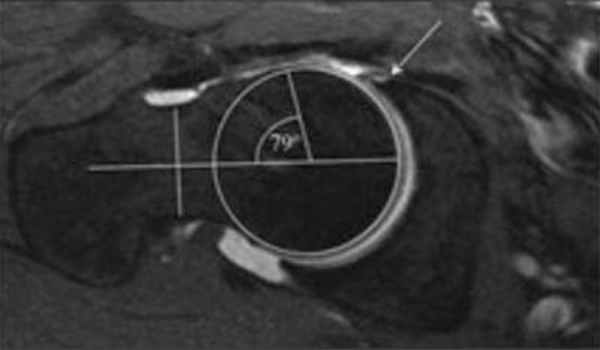

Рис. 1

В норме шейка бедра по отношению к фронтальной плоскости тела расположена под углом 12 градусов, мыщелки бедренной кости и стопа ориентированы вперёд. При антеверсии бедра шейка бедра по отношению к фронтальной плоскости тела располагается под более тупым углом, и вся нижняя конечность разворачивается латерально — мыщелки бедренной кости и стопа ориентированы кнаружи. При ретроверсии бедра шейка бедра по отношению к фронтальной плоскости тела располагается под более острым углом, и вся нижняя конечность разворачивается медиально — мыщелки бедренной кости и стопа ориентированы кнутри.

Рис. 2

В норме шейка бедра по отношению к плоскости мыщелков бедра расположена под углом 12 градусов, и стопа ориентирована вперёд. Обратите внимание, что на рисунке выше (см. рис. 2) первое изображение идентично первому изображению на рисунке ниже (см. рис.3). Это означает, что нормальная торсия и нормальная антеверсия равны. В таком случае, фронтальная плоскость тела и плоскость мыщелков бедра параллельны друг другу, что считается оптимальным положением бедра. При антеторсии шейка бедра по отношению к плоскости мыщелков бедра располагается под более тупым углом, а вся нижняя конечность поворачивается кнутри. При ретроверсии шейка бедра по отношению к плоскости мыщелков бедра располагается под более острым углом, а вся нижняя конечность разворачивается кнаружи. При попытке ориентировать конечность прямо, нарушается расположение головки бедра в вертлужной впадине.

Рис. 3

- антеверсия — вращает ногу наружу, антеторсия — вращает ногу внутрь.

- ретроверсия — вращает ногу внутрь, ретроторсия — вращает ногу наружу.

По отношению к анатомической форме вертлужной впадины используются понятия: угол покрытия головки бедра, глубина вертлужной впадины, угол наклона вертлужной впадины и угол антеверсии вертлужной впадины.

Чем глубже вертлужная впадина и больше угол покрытия головки бедра, тем сустав более стабилен, но возможны ограничения высокоамплитудных движений. Чем эти параметры меньше, тем сустав более мобильный, но менее стабильный. Кроме того снижение площади соприкосновения суставных поверхностей увеличивает давление на них. Таким людям нежелательно форсировать упражнения в крайних амплитудах подвижности.

Увеличенный угол наклона вертлужной впадины (угол Шарпа) характерен для врождённой дисплазии тазобедренного сустава. У взрослых данная патология встречается редко, обычно как продолжение детской дисплазии тазобедренного сустава.

При антеверсии вертлужной впадины возможно ограничение отведения бедра.

Рис. 4